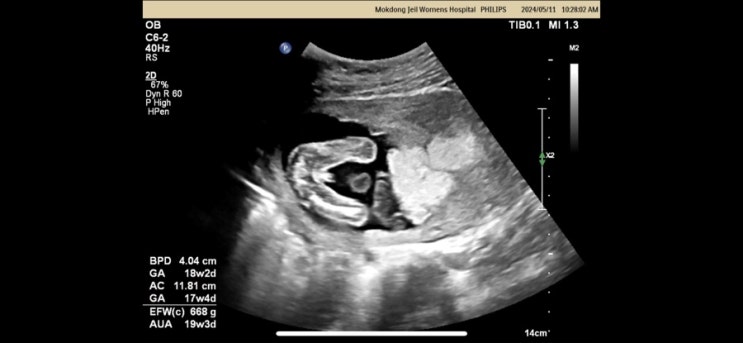

[태교일기] 임신 18주 : 날씨 좋은 한 주, 태동시작

임신 18주는 입덧이 많이 사라지고 날씨도 좋아 많이 즐겼던 주였다. 1. 보드게임 #신촌 #레드버튼 부처님...

[태교일기] 임신 17주- 태아보험 가입, 젠더리빌파티, 산부인과 진료

1. 태아보험 가입 #태아보험 태아보험은 11주 이내에 가입하는 것이 좋다고 한다. 근데 11주였을 시기 회사...